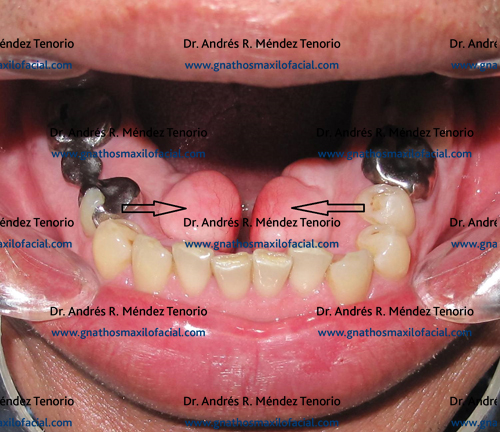

Otro problema que comúnmente afecta la confección de una prótesis es la presencia de restos radiculares múltiples, y las secuelas de extracciones dentales mal elaboradas en el pasado, que han producido irregularidad en el hueso, llamadas espículas óseas. El tratamiento en estos casos es la extracción dental, y la regularización del proceso alveolar.

![]() |

También se realiza regularización de proceso alveolar en los casos de enfermedad periodontal avanzada donde se deben extraer todos los dientes presentes, como en el siguiente caso: